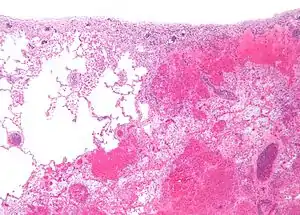

| Micrograph of a pulmonary infarct (right of image) beside relatively normal lung (left of image). H&E stain. | |

- Red infarctions (hemorrhagic infarcts) generally affect the lungs or other loose organs (testis, ovary, small intestines). The occlusion consists more of red blood cells and fibrin strands. Characteristics of red infarcts include: